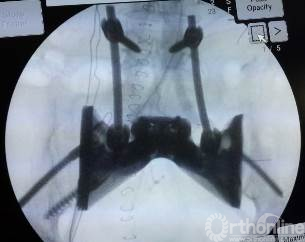

目前方兴未艾的3D打印技术为破解难题打开的新的大门。为了最大程度重建王力的骶骨缺损、恢复腰骶部连续性,保证术后的生活质量,郭卫教授应用3D打印技术,根据该患者骶骨切除术后骨缺损定制制造出空间结构解剖形态的人工全骶骨假体,其表面具有金属孔隙结构,可以允许骨细胞长入空隙金属内,假体与脊柱、骨盆连接,更符合生物力学结构的功能重建。

整台手术历时4小时成功完成,骶骨肿瘤彻底切除后,经过精心设计、反复修改的高订假体完美安放,与腰椎、骨盆紧密贴合,固定精准牢靠。国际首例应用3D打印特殊定制人工全骶骨假体进行骨缺损重建实现了完美首秀。这一假体及重建方式均为世界首创,为骶骨恶性肿瘤切除后骨缺损的重建方式开辟了一条崭新的途径。